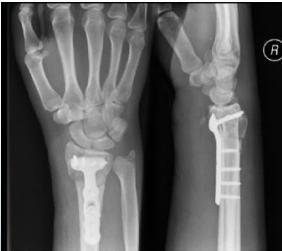

| Plate Types - Buttress Plate (T-Plate/L-Plate) | Indications: Lateral or medial tibial plateau fractures, distal radius fractures. | , , , ![]() |

| Plate Types - Anatomical Plates with Locked Screws | Indications: Metaphyseal fractures. Advantages: Anatomically contoured, excellent fixation in metaphyseal areas and osteoporotic bone. | , , ![]() |